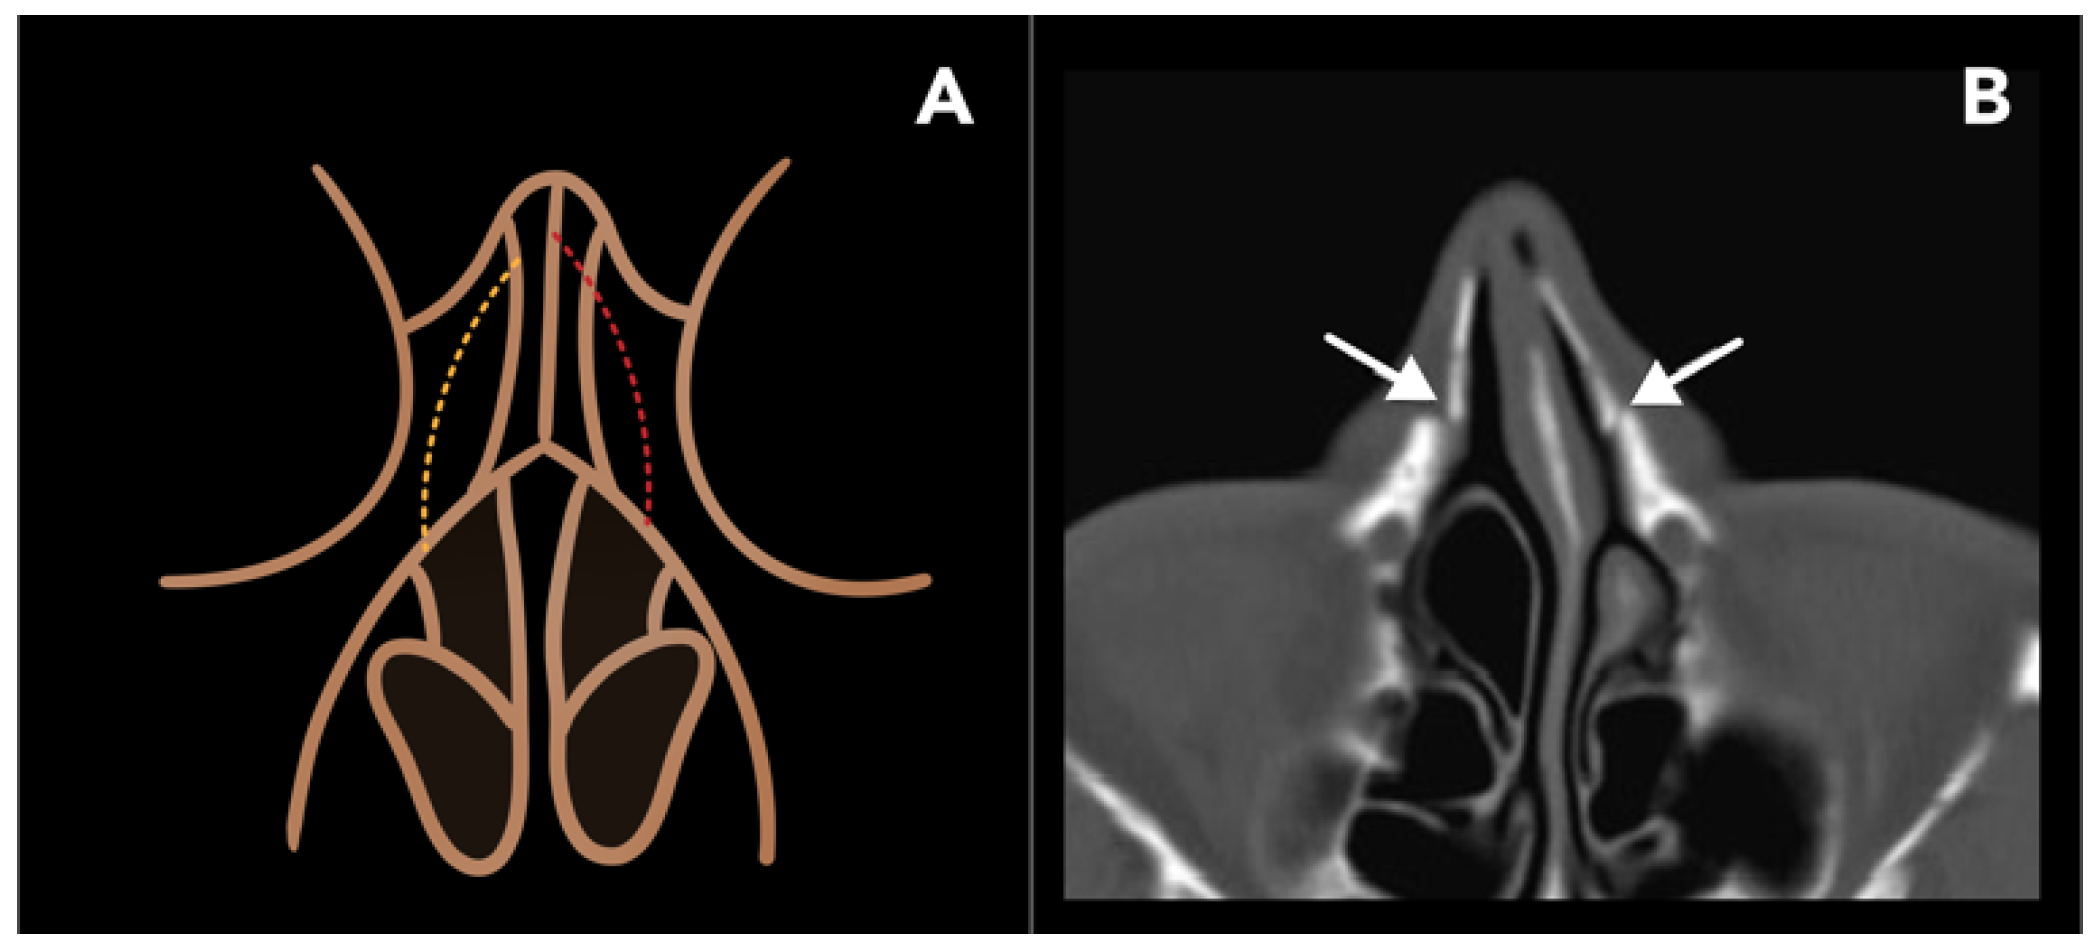

2.1.2. Lateral Nasal Osteotomy

2.1.3. Reduction Malarplasty